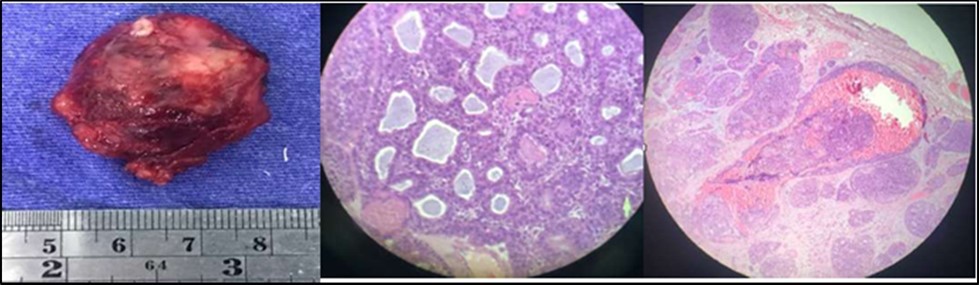

Histopathologic study described that the mass consisted of a piece of dark brown ovoid soft tissue measuring 3.5 x 3.2 x 1.5 cm .The external surface is rough with a mucosal defect measuring 0.8cm at its widest diameter. Cut sections show light brown, variegated solid surface. Microsections disclose sheets and nests of neoplastic cells forming solid and cribriform patterns .The histologic report showed adenoid cystic carcinoma with lymphovascular and perineural invasion. The surgical margins are positive for tumor involvement.

Figure 4.Orbital Mass, left 4B. Cribriform or Swiss-Cheese Pattern 4C. Lymphovascular and perineural invasion